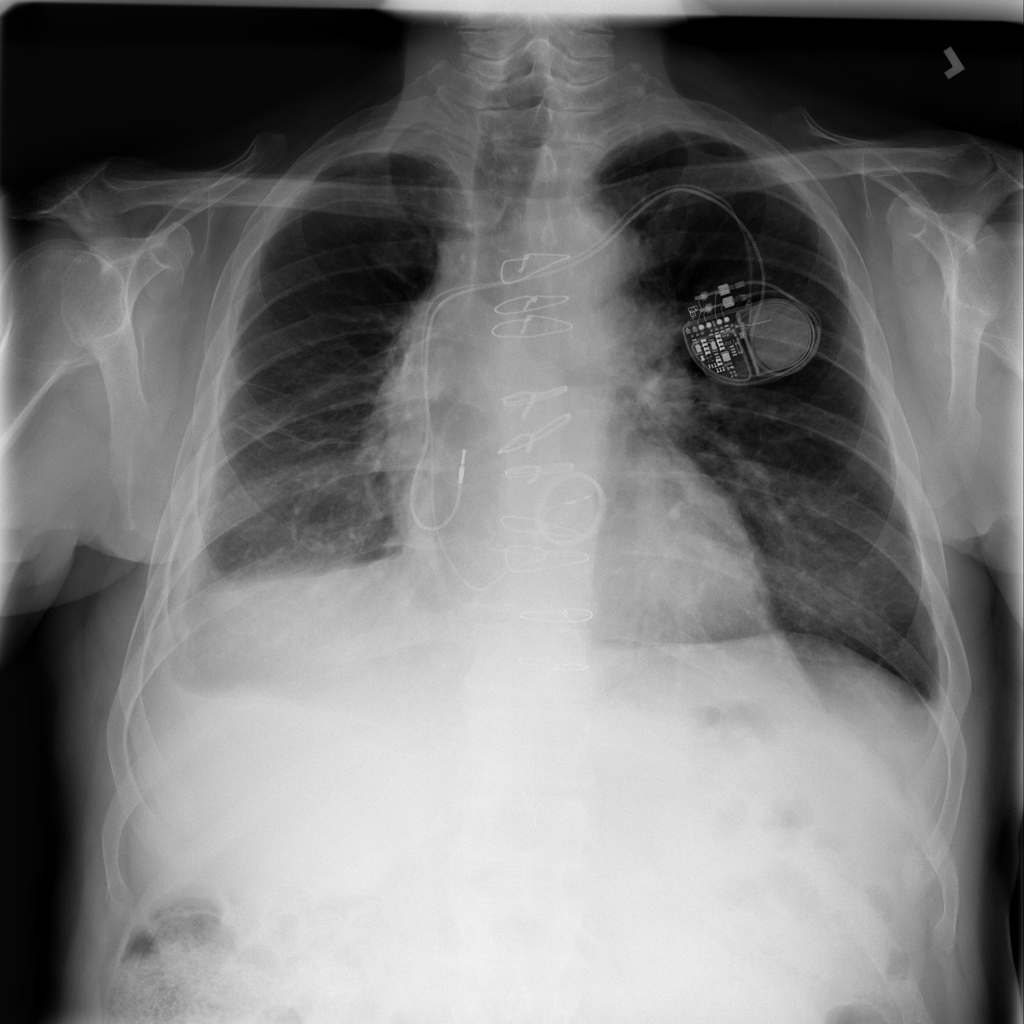

Showing up to 90 reference images for Nodule.

PAT-F3E7 · IMG-002Nodule

PAT-F3E7 · IMG-002

PA